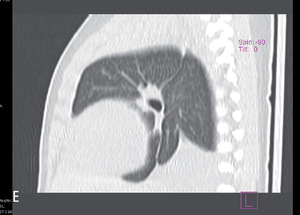

W piśmiennictwie medycznym większość publikacji na temat sekwestracji to zestawienia kilku do kilkunastu przypadków albo przeglądy piśmiennictwa.1,2,4,5 Największa przedstawiona grupa liczy 2625 chorych (zarówno dzieci, jak i dorosłych) i pochodzi z retrospektywnej analizy bazy danych, rejestrującej dobrze udokumentowane przypadki opisane w chińskim piśmiennictwie w latach 1998-2008.6 W tym materiale sekwestracje wewnątrzpłatowe stanowiły 84%, a zewnątrzpłatowe 16%. W obrazie radiologicznym sekwestracja przedstawiała się jako zmiany guzowate (46%), torbielowate (37%), jamiste (6%) lub naśladujące zmiany zapalne (10%). W obrazie tomografii komputerowej wysokiej rozdzielczości (HRCT) tych samych chorych uzyskano obraz zmian guzowatych (49%), torbielowatych (29%), jamistych (12%) lub naśladujących zmiany zapalne (8%) albo rozstrzeniowe (2%). U pojedynczych chorych zmiany miały obraz otorbionego wysięku.

Rycina 2. Zdjęcia przeglądowe tylno-przednie (A) i boczne (B) dwutygodniowej dziewczynki z sekwestracją zewnątrzpłatową lewego płuca.

Rycina 3. Zdjęcia przeglądowe tylno-przednie (A) i boczne (B) trzymiesięcznego chłopca z sekwestracją wewnątrzpłatową dolnego płata prawego.